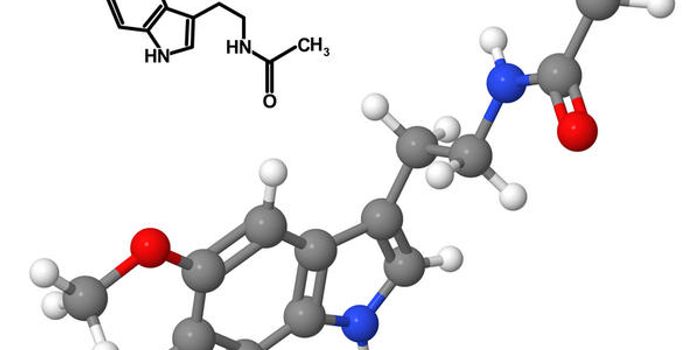

JUN 02, 2016Plants & AnimalsPsilocybin is the active ingredient in ‘magic mushrooms’ that leads to hallucinations and other psychologica ...